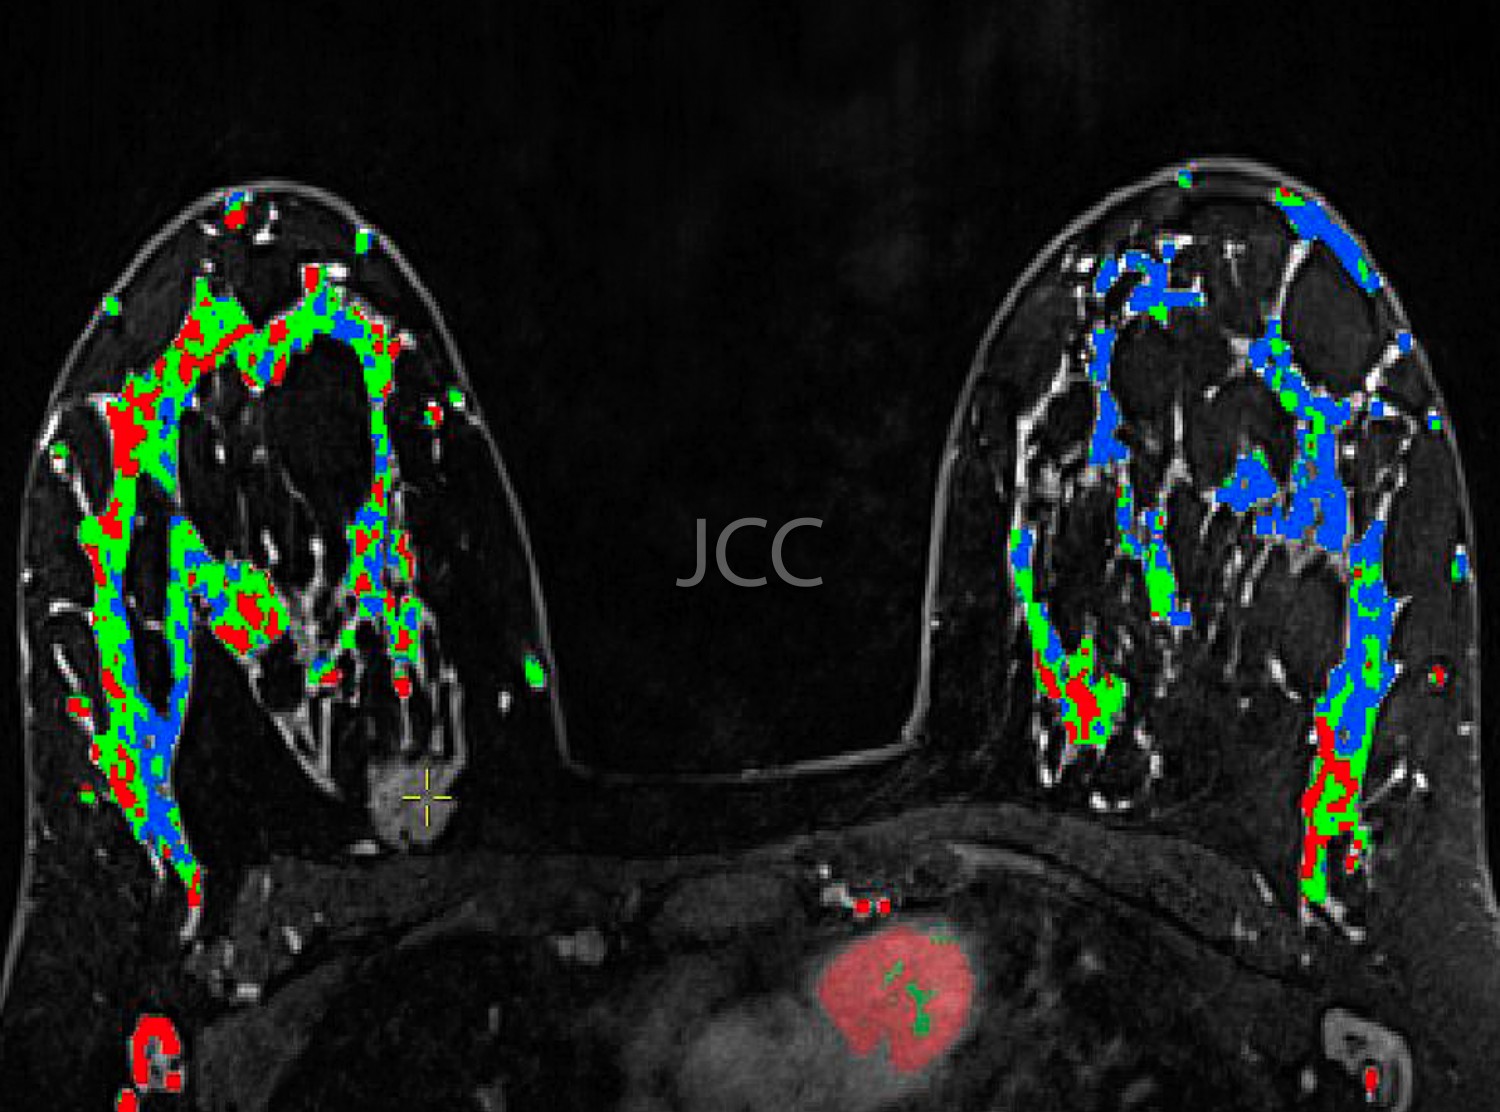

A introdução dos mais recentes sistemas de tomografia computorizada Dual-Source, primeiros equipamentos destes instalados em Portugal – Siemens Somaton Definition FLASH e DRIVE, com dupla ampola e duplo detector, permite a aquisição de 256 imagens em 0.28 segundos, utilizando-se uma dose de radiação muito reduzida, bastante inferior à utilizada, nomeadamente nos equipamentos de 64 cortes, geralmente utilizados para avaliação cardíaca, nomeadamente das artérias coronárias. Associamos ao nosso programa de rastreio a última tecnologia em ressonância magnética 3 tesla para despiste de patologias cerebral, prostática e mamária.

• RM Mamária